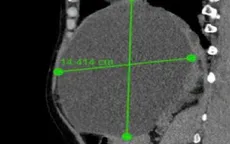

VTV.vn - Nang gan thường không triệu chứng nhưng khi kích thước lớn có thể chèn ép gan, gây đau tức, ảnh hưởng sức khỏe. Phát hiện sớm và theo dõi định kỳ giúp phòng biến chứng.